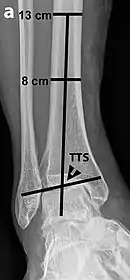

Varus or valgus deformity, if suspected, can be measured with the frontal tibiotalar surface angle (TTS), formed by the mid-longitudinal tibial axis (such as through a line bisecting the tibia at 8 and 13 cm above the tibial plafond) and the talar surface.[23] An angle of less than 84 degrees is regarded as talipes varus, and an angle of more than 94 degrees is regarded as talipes valgus.[24]